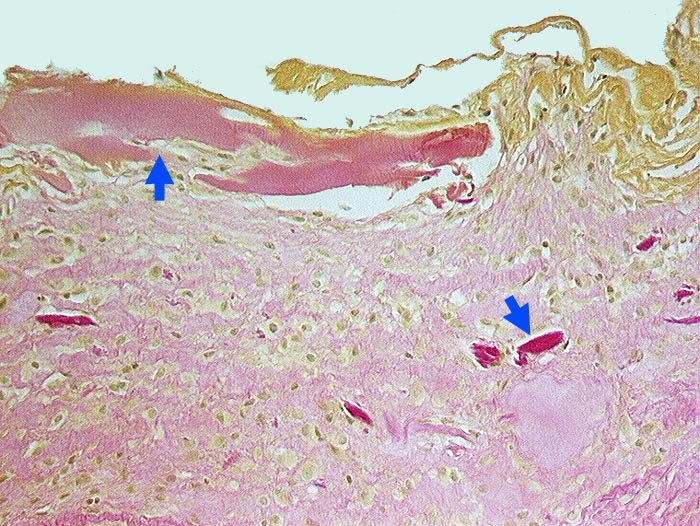

Detritussynovialitis

Entzündung / Reparatur

Synovialis

Knochen, Knorpel, Gelenke

Fibrosierte Synovialis mit gelben Fibrinauflagerungen. Infiltratfreies Stroma mit zahlreichen avitalen Knochenfragmenten.

Gonarthrose mit Nekrose der Tibiakondylen.